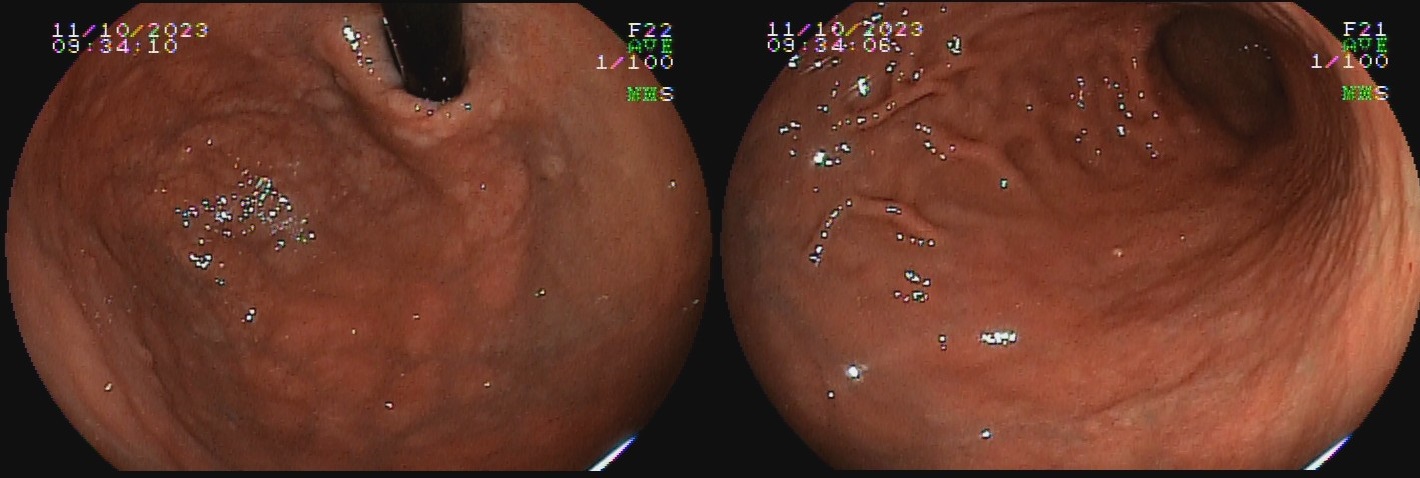

O termo gastrite crônica atrófica refere-se à atrofia da mucosa gástrica causada pelo H. pylori. Inicialmente, a mucosa sofre agressão por neutrófilos, e mais tardiamente, por monócitos. Com o tempo, essa agressão reduz a população de glândulas, tornando o relevo reduzido e a mucosa mais pálida. A diminuição da espessura da camada mucosa torna os vasos da submucosa mais evidentes ao exame endoscópico. Segundo a evolução descrita por Kimura-Takemoto, essa patologia tem início no antro e incisura angular (C1),  e progride em direção à cárdia pela pequena curvatura do corpo, e, após atingir a região mais proximal do estômago (C2 e C3), a progressão inicia abertura da região acometida, expandindo-se em direção às paredes anterior e posterior do corpo e fundo simetricamente (O1 e O2), até acometer a grande curvatura (O3).